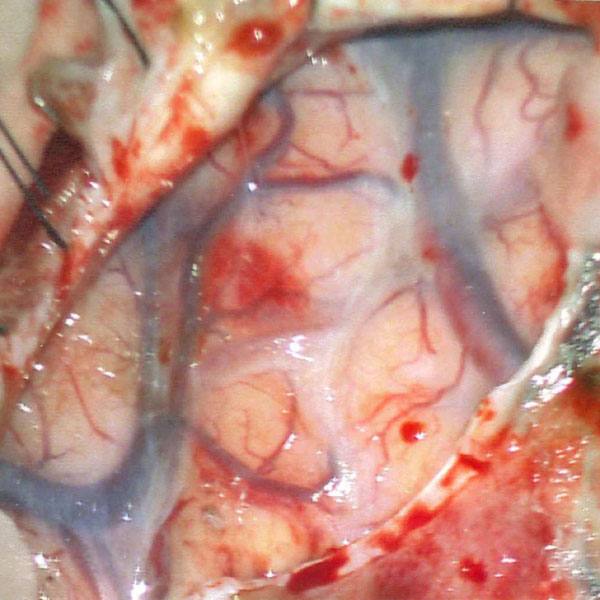

'19年5月

30代

富永/久貝

右中小脳脚 出血再発

SM 3(S1,E1,V1)

米国の病院

No.359 モニタリング

No.359 手術前

No.359 手術中

No.359 手術後

出血既往があり。2回の手術前血管内手術の後に、

Lateral transpeduncular approachにより再々出血予防を目的に

摘出手術を行う。完全摘出であることを確認した。

手術による合併症や後遺症なしで退院した。経過良好。